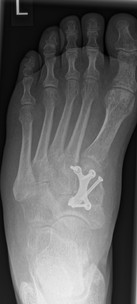

3.- April 2017: Schraubenbruch

Im Rahmen einer Verlaufskontrolle zeigte sich ein Schraubenbruch als Zeichen einer fehlenden Durchbauung der Arthrodese.

Es wurde die Indikation zur Revisionsoperation mit Rearthrodese gestellt. Diese wurde im Juni 2017 durchgeführt.